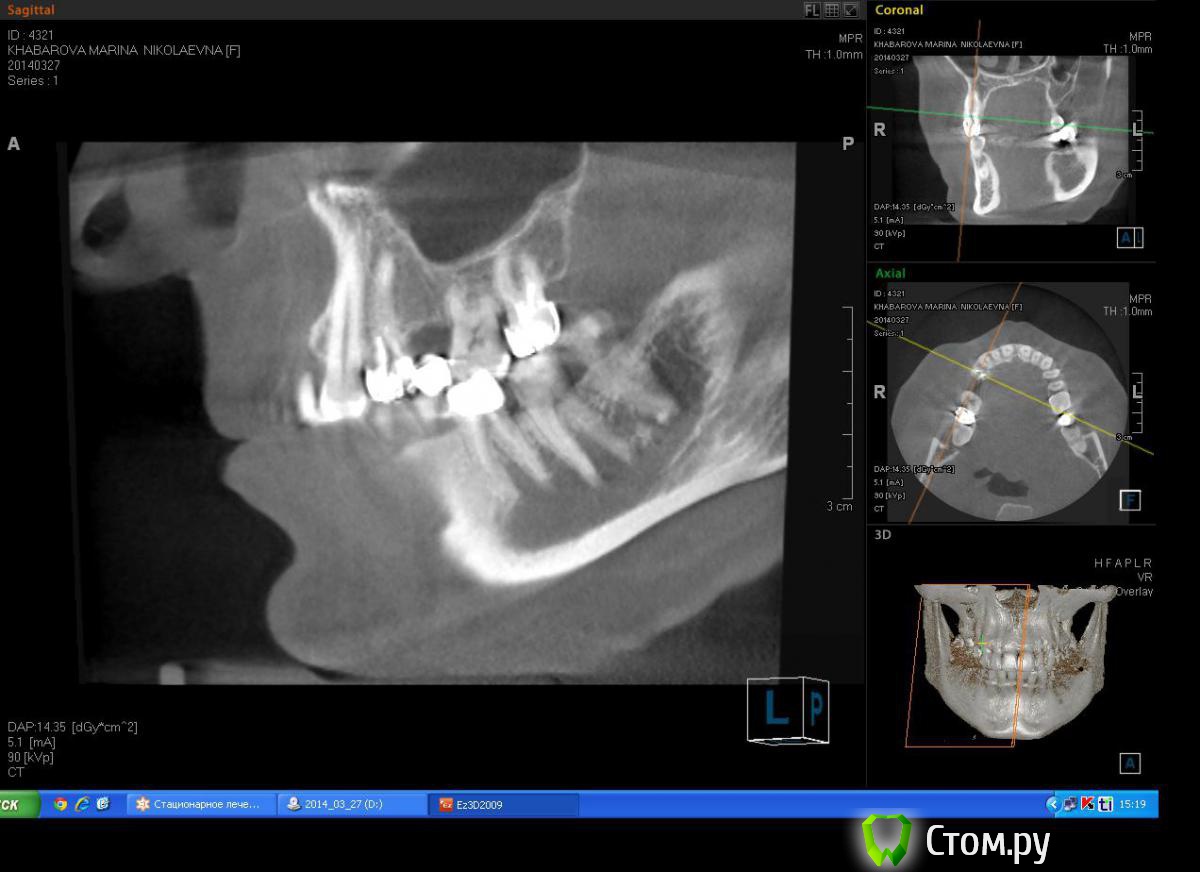

Milanomoda Опубликовано 22 апреля, 2014 Поделиться Опубликовано 22 апреля, 2014 Здравствуйте, уважаемые коллеги. Вообщем обратилась за помощью пациентка - в области 14 зуб, от него консоль на 15, посоветовавшись с ортопедом, приняли решение удалить 14 зуб и одномоментно в лунку имплант, в это же посещение имплантация в области 15. Подскажите пожалуйста с тактикой, можно ли в данном случае рассматривать одномоментную методику имплантации ? Заранаее с пасибо ) Снимки КТ прикладываю. Ссылка на комментарий

Milanomoda Опубликовано 22 апреля, 2014 Автор Поделиться Опубликовано 22 апреля, 2014 Альфа био , SPI. В область 15 планирую 4.2х8 , в область 14 - 4.2 на 13 либо 16 mm, пока что еще думаю...Костный материал - Bioss Ссылка на комментарий

DShu Опубликовано 22 апреля, 2014 Поделиться Опубликовано 22 апреля, 2014 4,2 думаю им там тесновато будет. 4,5 тем более.На 14 я бы поставил 3,75*16 (или на 13) на 15 - 3,75*10 бикортикально. Сразу формики, вокруг - графт или без него, кто как любит) 3 Ссылка на комментарий

Milanomoda Опубликовано 22 апреля, 2014 Автор Поделиться Опубликовано 22 апреля, 2014 4,2 думаю им там тесновато будет. 4,5 тем более.На 14 я бы поставил 3,75*16 (или на 13) на 15 - 3,75*10 бикортикально. Сразу формики, вокруг - графт или без него, кто как любит)Если в области 15 делать бикартикальную фиксацию то без синуса(закрытого) не обойтись, а если делать без синуса - то при нагрузке мне кажется слизистая гайморовой среагирует, не даром же от анатомических образований рекомендуют около 2 мм отступать... Ссылка на комментарий